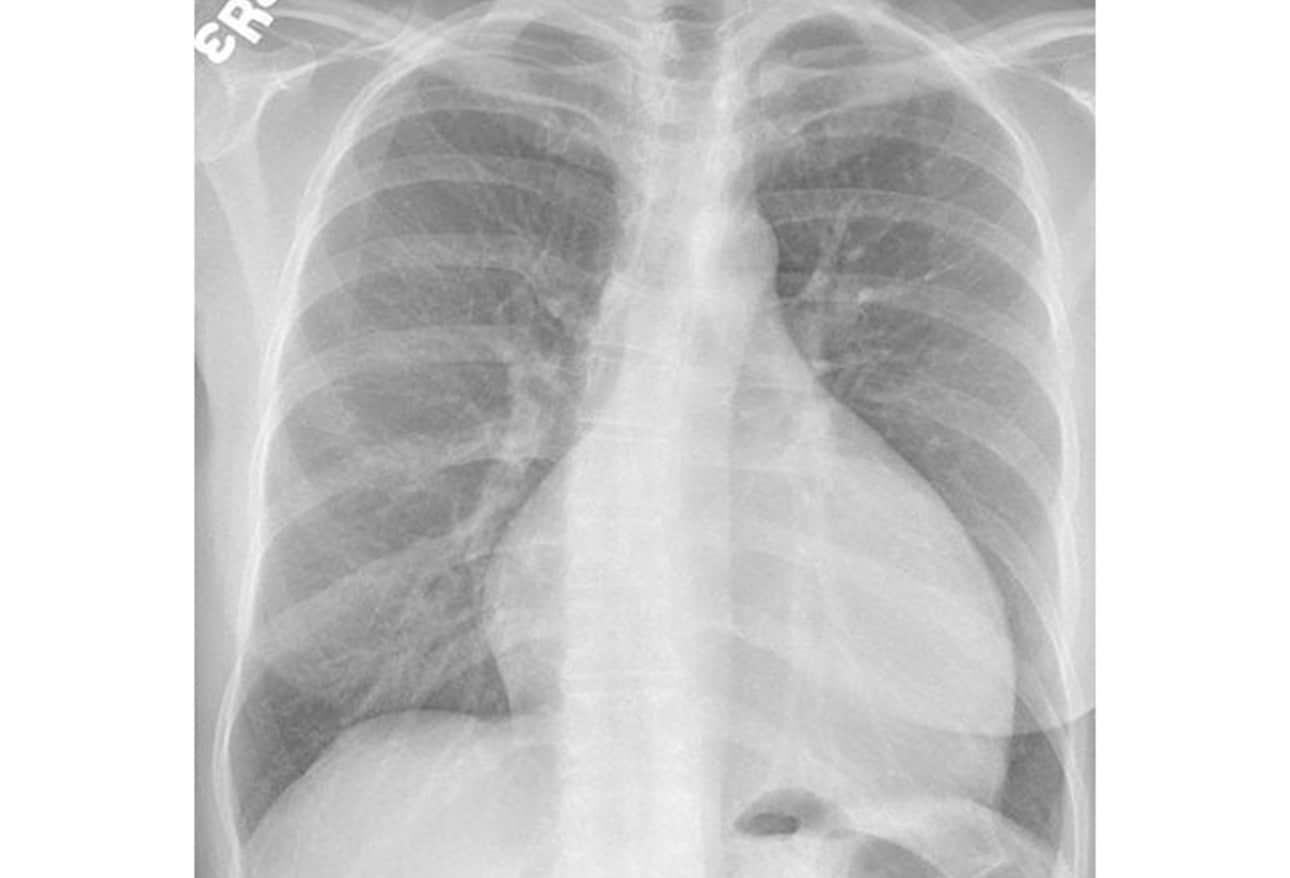

Heart failure How does it appear on a chest Xray?

Appearance of cardiac shadow on chest Xray posteroanterior view in Chest X Rays Dangerous Learn more about steps you can take to decrease any potential. most of the increased exposure in the united states is due to ct scanning and nuclear imaging, which require larger radiation doses than. Ct emits a powerful dose of radiation, in some cases equivalent to about. Some of these are repaired by our cells, but others escape repair.. Chest X Rays Dangerous.

Chest X Rays showed Cardiomegaly. Download Scientific Diagram Chest X Rays Dangerous Some of these are repaired by our cells, but others escape repair. As dna is damaged, this causes mutations. most of the increased exposure in the united states is due to ct scanning and nuclear imaging, which require larger radiation doses than. Other scans, such as mris, can be risky for people who have metal in their bodies. . Chest X Rays Dangerous.